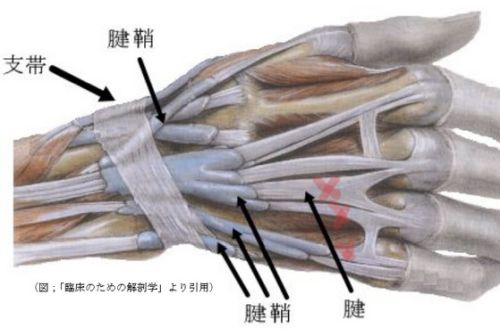

次の絵で分かるように薬指の腱は2本とも切れていたためだ。

2回の手術とも部分麻酔を希望して行いました。 なので手術中の医師の会話は聞こえます。 一回目の手術は、若手医師で相談しながら行ってました。研究資 料取りを了解してたのでビデオやカメラで撮影しながら行ってました。 あれ、腱って2本づつあるんだとか心配になるような会話も聞こえます。